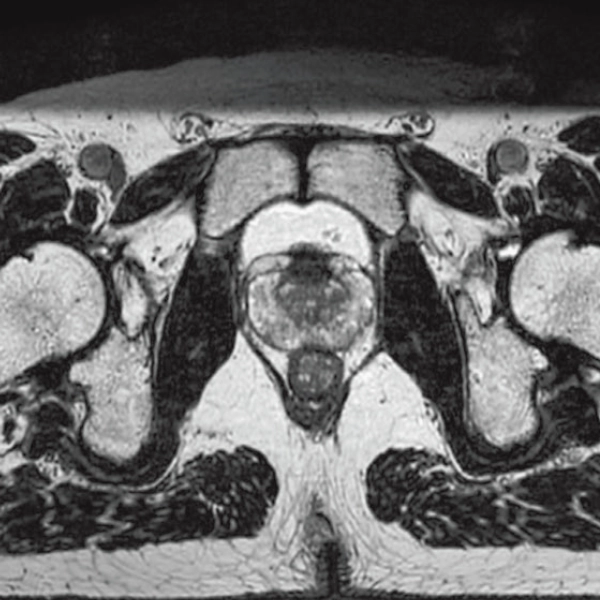

DLR offers 2 options

High Resolution

T2WI, 0.56×0.70×3.0mm, 2:28

3D Bone

0.93×0.93×1.2(0.6)mm

1.1×1.1×1.2(0.6)mm